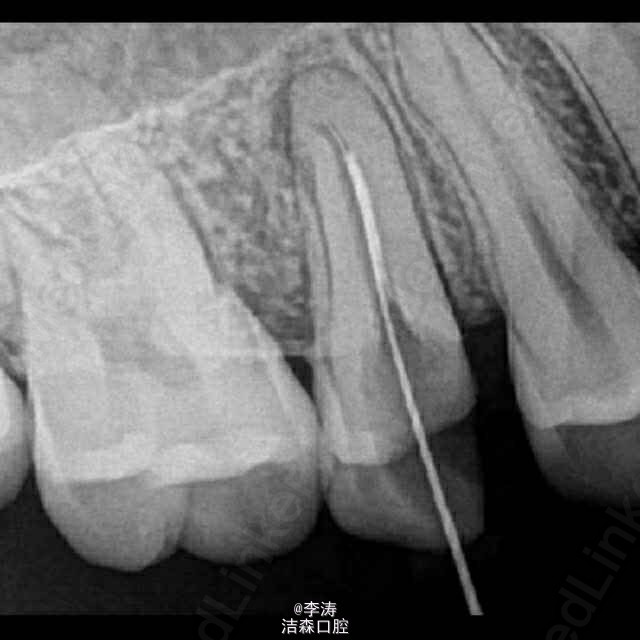

过台阶根管再治疗一例

15牙因根管治疗后牙折裂,行根管再治疗

年轻恒牙;根管再治疗;消除台阶